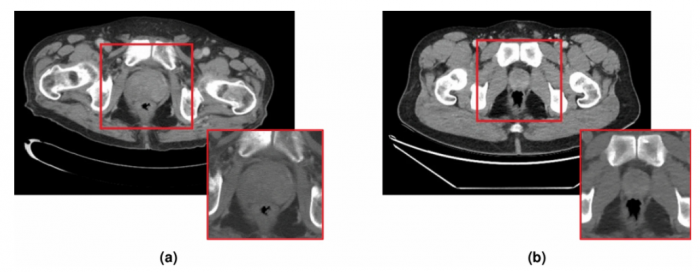

这方面的最新例子来自皇家墨尔本理工大学和圣文森特医院的研究人员,他们从患有和未患有前列腺癌的无症状患者的CT扫描开始。科学家们指出,一般来说,CT扫描对检测骨骼和关节问题等疾病很有用,但放射科医生很难用它们来检测前列腺癌。

利用CT扫描,人工智能软件被训练来搜索可能表明该疾病的不规则现象。该工具随着每次扫描的进行而改进,完善其能力并适应分析不同机器的扫描,最终发现疾病的最小特征。随着时间的推移,它能够胜过放射科医生,在几秒钟内检测出癌症的生长,甚至在病人出现任何症状之前。